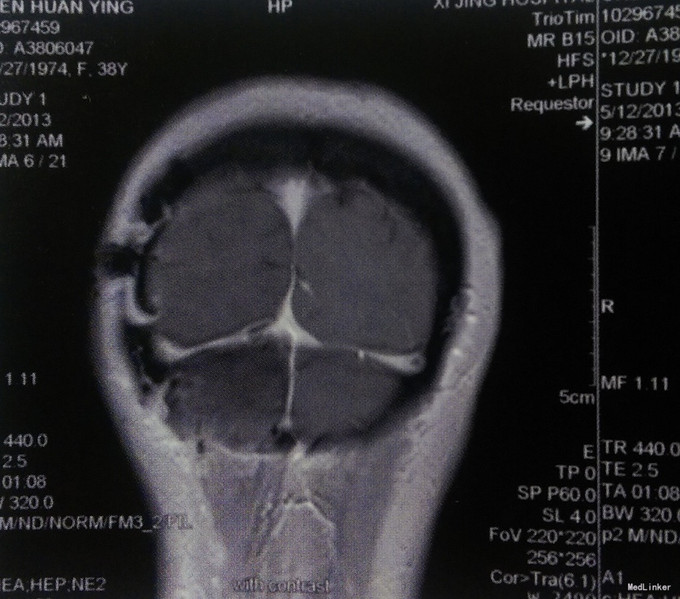

治疗期间恢复顺利,头痛、头晕症状明显改善,头部切口甲级愈合。病理检查:右侧小脑幕脑膜瘤(WHO Ⅰ级)。出院后未行其他辅助治疗,嘱定期复查。 术合3个月行MRI检查:右侧小脑幕脑膜瘤完全切除,无复发。